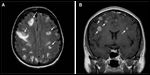

FIGURE 1

MRI of Brain Metastases

Patients with brain metastases typically present with signs of focal neurologic dysfunction. These symptoms include seizures and focal motor or sensory deficits. The diagnosis requires use of imaging studies (magnetic resonance imaging [MRI] is the most sensitive method) and possibly a pathologic confirmation (surgical biopsy or resection), and infrequently involves the need to sample the cerebrospinal fluid (Figure 1).